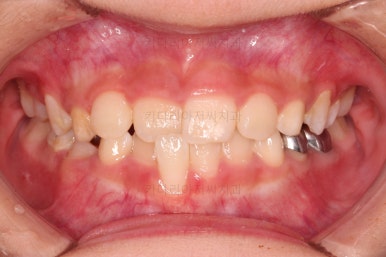

CASE 2.

나이 : 8세

총 치료기간 : 2주(2달 아님, 2주 맞음)

대신 앞니가 거꾸로 물려있어 웃는 모습부터 드러나는 치열의 모습까지 부자연스러운 모습인데요.

이번 환자분도 치료가 굉장히 빨리 끝났어요.

2주만에 해결!

장치도 굉장히 심플하고, 비용도 매우매우 저렴하답니다.

같은 문제를 고급 장치를 이용해서 비싸게 치료할 수도 있지만 목표치가 적당하다면 매우 좋은 치료라고 생각합니다.

바로 부산어린이교정 전후사진 비교해 볼게요.

단, 2주만에 문제시 되는 딱 한 개의 치아에만 포커스를 맞춰 해당 치아 반대교합만 개선해준 매우 훌륭한 치료였습니다.

이상 매우 간단한 장치로 매우 빠르게 반대교합을 치료한 부산어린이교정 두 명의 치료사례였습니다.